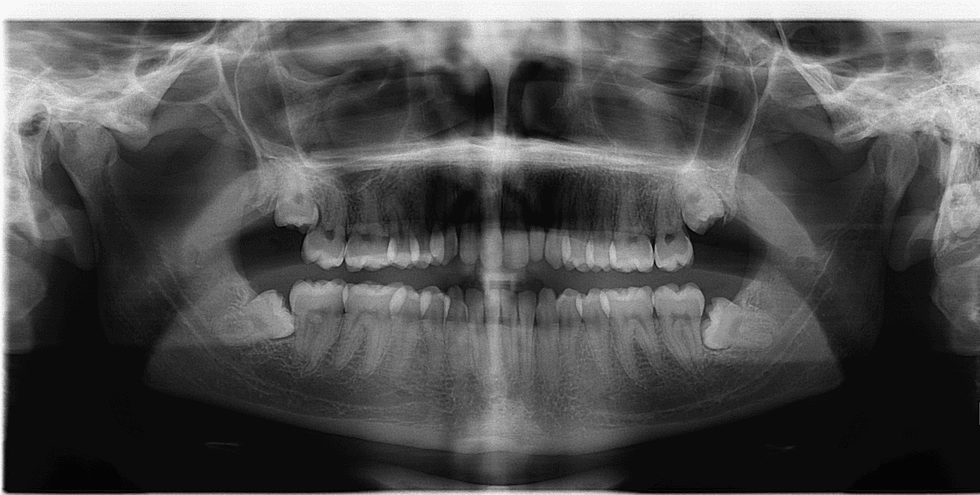

For example, while all of my other friends were getting shwasted and frolicking around during Spring Break 2017, I spent the sweet time getting my wisdom teeth yanked out of my mouth. This is purely because I am graduating early, and I have no other time to fit this procedure into my schedule, so I gotta do what I gotta do.